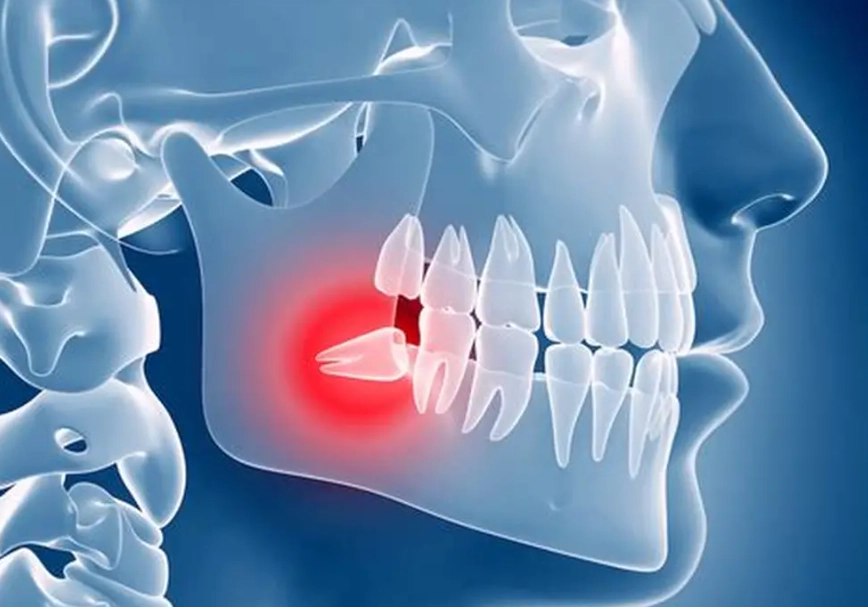

Think of a cyst as a biological balloon. It's a closed sac lined with cells and filled with fluid—sometimes thin and watery, sometimes thick and mucus-like. When it forms around the crown of an unerupted tooth (like a wisdom tooth stuck in the jaw), it's specifically called a dentigerous cyst.

Here’s the basic mechanics: as a wisdom tooth tries to erupt, the follicle (the tissue sac surrounding it) can sometimes get stimulated and start producing fluid abnormally. This fluid builds up, creating pressure that slowly expands the sac and, critically, erodes the surrounding jawbone to make space for itself. It doesn't invade the bone aggressively like cancer; it politely—but destructively—remodels it.

Numbness or Tingling: This is a red flag. If the cyst grows large enough to press on the inferior alveolar nerve (the nerve that gives feeling to your lower lip and chin), you might experience numbness or a pins-and-needles sensation. This signals significant size and potential nerve involvement.